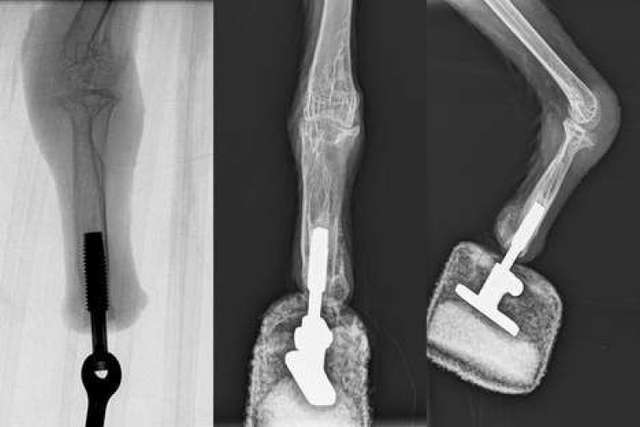

Після огляду фахівці вирішили створити спеціальний біонічний протез. Такі протези вже раніше встановлювали людям, але досі ніколи — птахам.

Біонічний імплантат було встановлено за технікою остеоінтеграції, або приєднання протеза безпосередньо до кістки. Операцію проводили в кілька етапів. Спершу завдяки остеотомії у кістці просвердлили отвір, у який потім вставили імплантат. Далі на нього одягли протез, що сполучається з імплантатом через шарнір. Сам протез вкритий кількома шарами м’якого і в’язкого матеріалу, щоб не викликати тертя й витримувати навантаження на лапу.